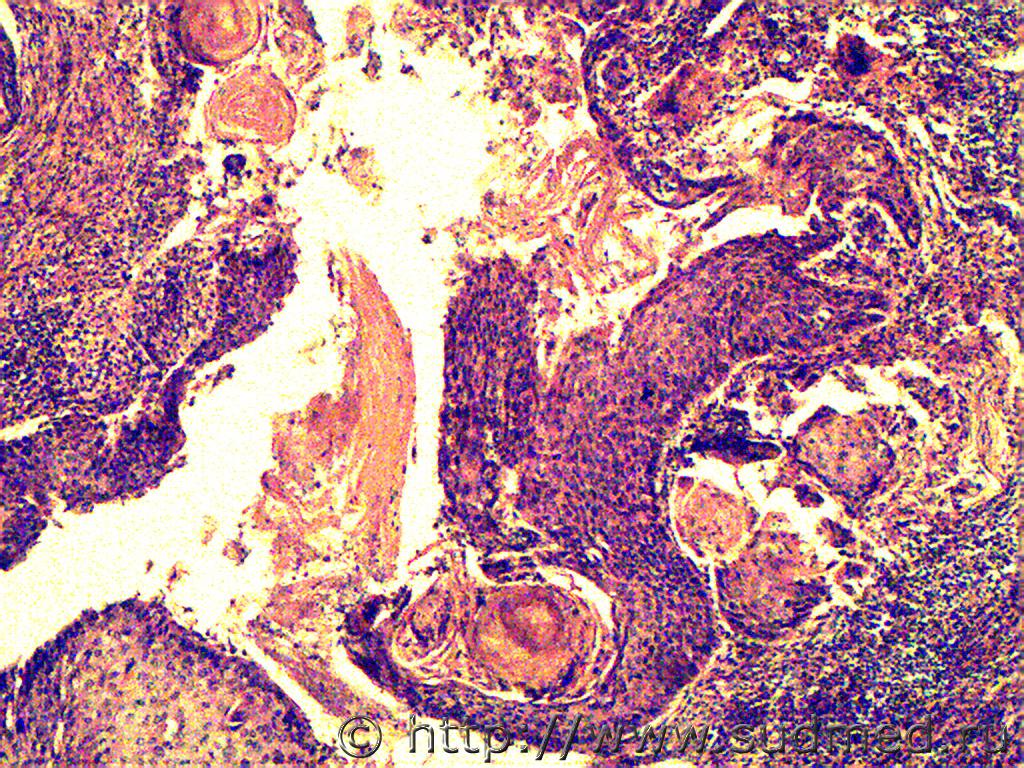

Anton То кератоакантома. Однако, онкоморфологов надо. 13.11.2013 - 18:44

Медик кератоакантома.

Мысль была,но здесь клеточный по... 13.11.2013 - 19:44

Smeks1 Уважаемые коллеги, мое мнение - плоскоклеточный, G... 15.11.2013 - 13:10

jaklin Плоскоклеточный рак, т.к. есть жемчужины. 20.11.2013 - 19:17